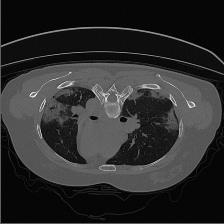

Medical image segmentation is one of the most fundamental tasks concerning medical information analysis. Various solutions have been proposed so far, including many deep learning-based techniques, such as U-Net, FC-DenseNet, etc. However, high-precision medical image segmentation remains a highly challenging task due to the existence of inherent magnification and distortion in medical images as well as the presence of lesions with similar density to normal tissues. In this paper, we propose TFCNs (Transformers for Fully Convolutional denseNets) to tackle the problem by introducing ResLinear-Transformer (RL-Transformer) and Convolutional Linear Attention Block (CLAB) to FC-DenseNet. TFCNs is not only able to utilize more latent information from the CT images for feature extraction, but also can capture and disseminate semantic features and filter non-semantic features more effectively through the CLAB module. Our experimental results show that TFCNs can achieve state-of-the-art performance with dice scores of 83.72\% on the Synapse dataset. In addition, we evaluate the robustness of TFCNs for lesion area effects on the COVID-19 public datasets. The Python code will be made publicly available on https://github.com/HUANGLIZI/TFCNs.